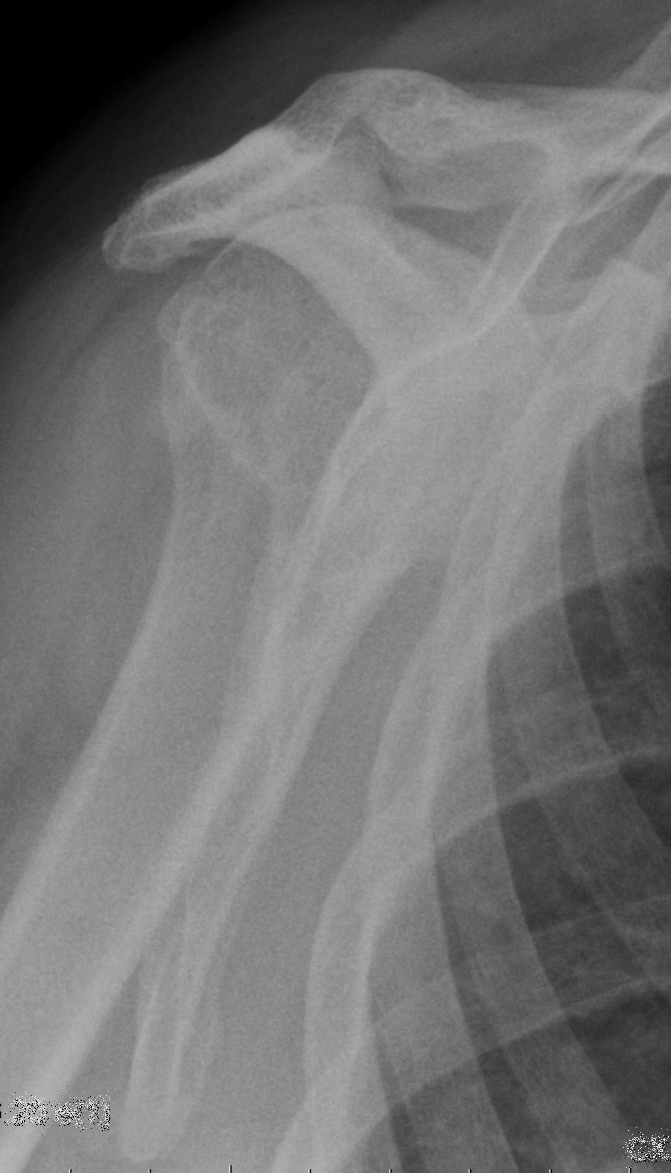

Beschreiben Sie die Befunde auf dem vorliegenden Röntgenbild der Schulter und geben Sie die wahrscheinlichste Ursache für die Befunde an.